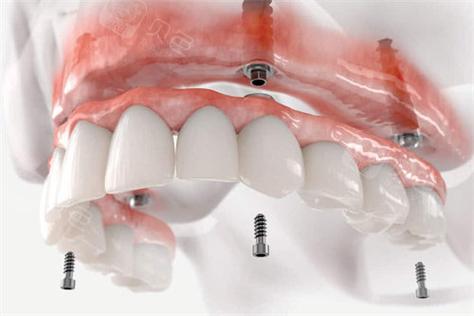

对于全口或半口牙缺失患者,All-on-4/6技术结合种植桥架可实现“当天种植、当天戴牙”的即刻负重效果,该技术通过植入4颗(All-on-4)或6颗(All-on-6)种植体,利用钛合金或氧化锆桥架将种植体连接成整体,上部制作固定义齿,即刻恢复患者咀嚼功能,桥架在此类修复中需具备极高的整体强度和抗变形能力,以支撑全口义齿的长期使用,数字化技术的应用(如术前CBV规划、3D打印桥架)可确保种植体位置精准,桥架与颌骨贴合度达95%以上,大幅提升手术效率和修复效果,尤其适用于希望快速恢复生活质量的患者。